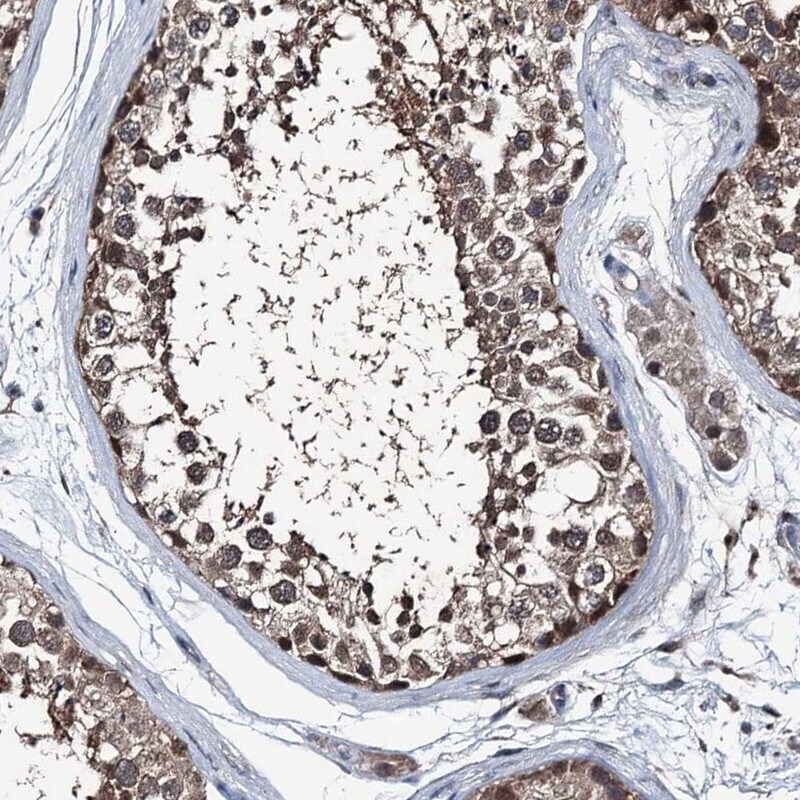

Supportive validation

- Submitted by

- Invitrogen Antibodies (provider)

- Main image

- Experimental details

- Immunohistochemical staining of PSMD13 in human testis using a PSMD13 Polyclonal Antibody (Product # PA5-58497) shows moderate cytoplasmic and nuclear positivity in cells in seminiferous ducts and Leydig cells.